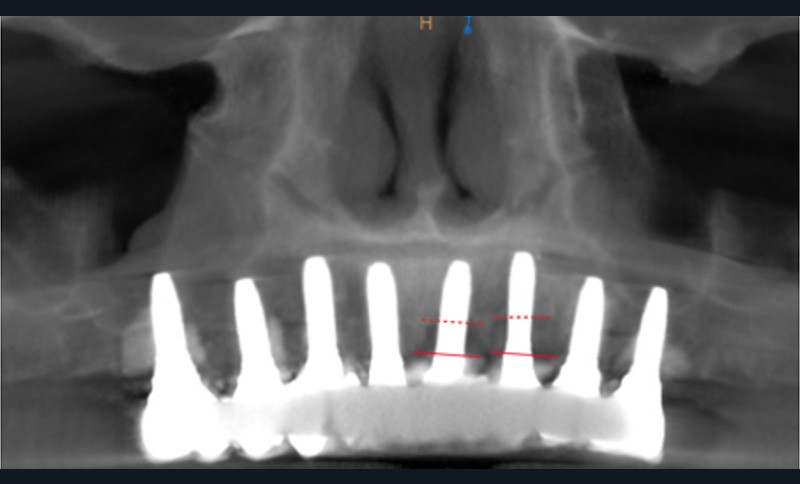

2 – Une méta analyse de 2016 [3] a évalué l’efficacité du traitement non chirurgical de la péri-implantite. Il s’avère que le traitement non chirurgical ne permet qu’une diminution de l’inflammation au niveau des tissus mous à court terme. En effet, on observe une diminution significative du saignement au sondage, mais pas de diminution efficace de la profondeur de sondage. En revanche, sans traitement chirurgical, on note une progression importante de la perte osseuse. Le traitement non chirurgical…